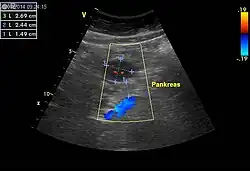

Ultraschallbild eines histologisch gesicherten gastrointestinalen Stromatumors (GIST, 2-3) ventral der Bauchspeicheldrüse (1). Querschnitt

Einen wesentlichen Beitrag zur Tumordiagnose und Bestimmung der Tumorausbreitung liefern bildgebende Verfahren wie Sonografie, konventionelle Röntgenaufnahmen nach Verabreichung von Kontrastmitteln, die Computertomografie sowie die Magnetresonanztomografie. Die Positronenemissionstomografie (PET) unter Verwendung von 18F-2-Fluor-2-deoxy-D-glucose eignet sich speziell zur Erfassung von Metastasen.[3]